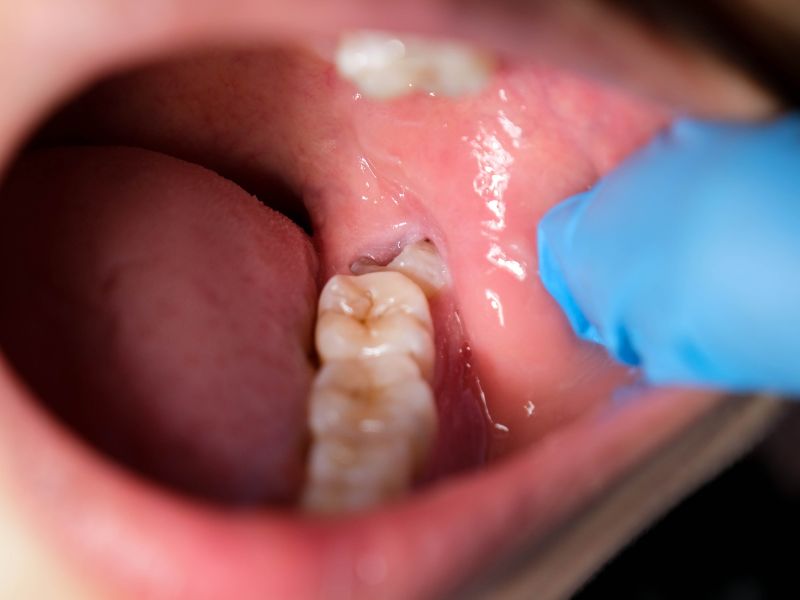

Wisdom teeth come in long after the rest of your smile has settled. That late arrival often puts them at odd angles. Some stay stuck under the gums, some push against the molars you already rely on, and others peek through halfway and collect bacteria.

When wisdom teeth only partially erupt, they create deep, hard-to-clean spaces. Food and bacteria settle in easily, which leads to infections or irritation. Removing the tooth removes the pocket.